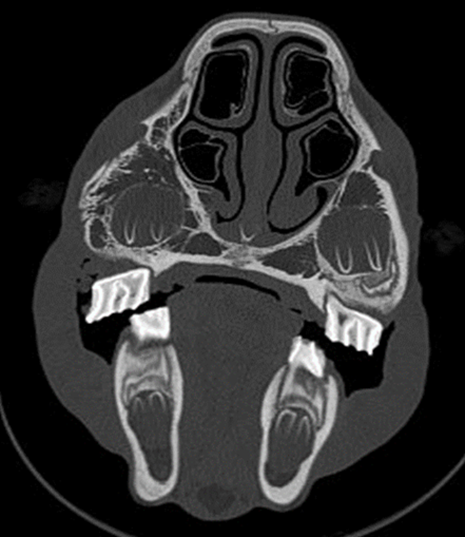

Diagnostic imaging identified the fractures to be complete and comminuted in all cases. The skull fractures were unilateral in 10 horses and bilateral in 3 cases. The most common facial bones involved were the maxilla in 9 horses, the nasal bone in 7 horses, and the frontal bone in 4 horses. The nasolacrimal duct was involved in 3 horses and the infraorbital canal in 1 horse. Secondary sinusitis was present in 10 horses with the rostral maxillary, caudal maxillary sinus, and ventral conchal sinus being the most affected. There was an associated fracture of dental structures in 3 horses (Figure 2a and Figure 2b).

Treatment was strictly conservative in half of the cases, consisting of wound treatment and systemic antibiotics and anti-inflammatories, as needed. In the other half of the cases, some minimal surgical intervention was undertaken and included removal of loose bony fragments and sinus trephine and sinoscopy, fragment removal and sinus flush through a Foley catheter and dental extraction. In most cases, the lacerations were cleaned, debrided, and closed primarily using either simple interrupted or tension-relieving sutures (vertical mattress). In certain cases, given the nature of the laceration, only partial closure was possible leaving a defect to heal by second intention. (Figure 2a)